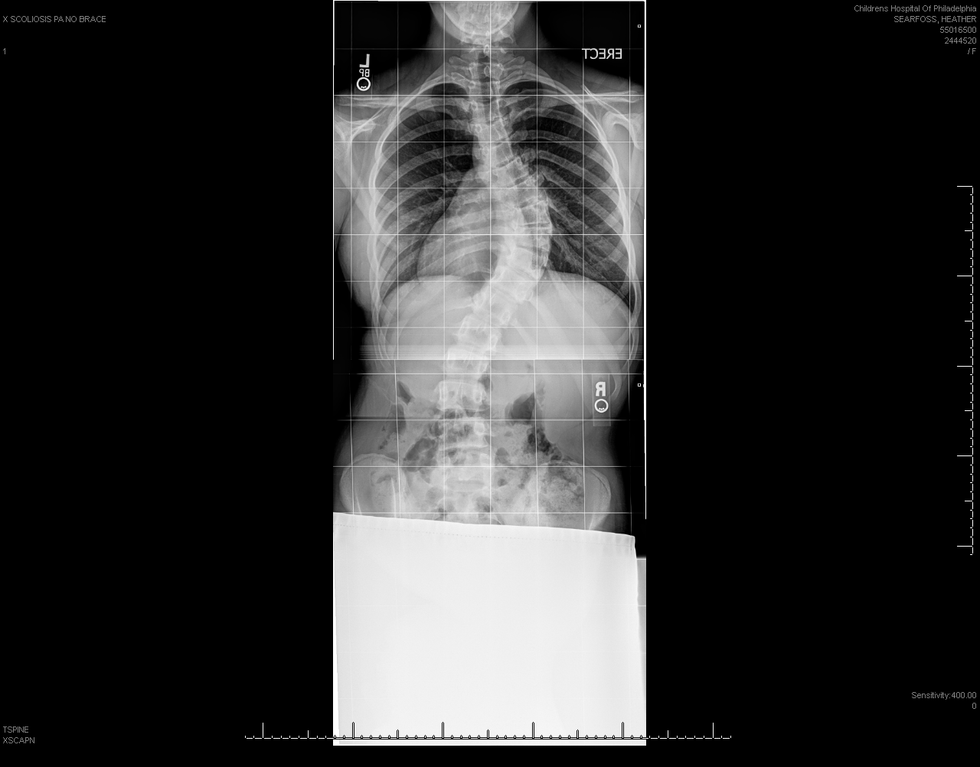

I had 2 curves in my spine.

One curvature was 65 degrees which caused my rib cage on my right side to protrude and constrict my left lung cavity and, the other was 32 degrees which caused my hips to protrude towards the left side. Altogether my curvatures were 97 degrees. By the summer of 2008 my curvatures would have escalated to 100 degrees or above.